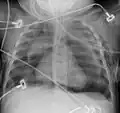

Pneumomediastinum is uncommon and occurs when air leaks into the mediastinum. The diagnosis can be confirmed via chest X-ray showing a radiolucent outline around the heart and mediastinum or via CT scanning of the thorax.

Pneumomediastinum with angel wing sign[15] -